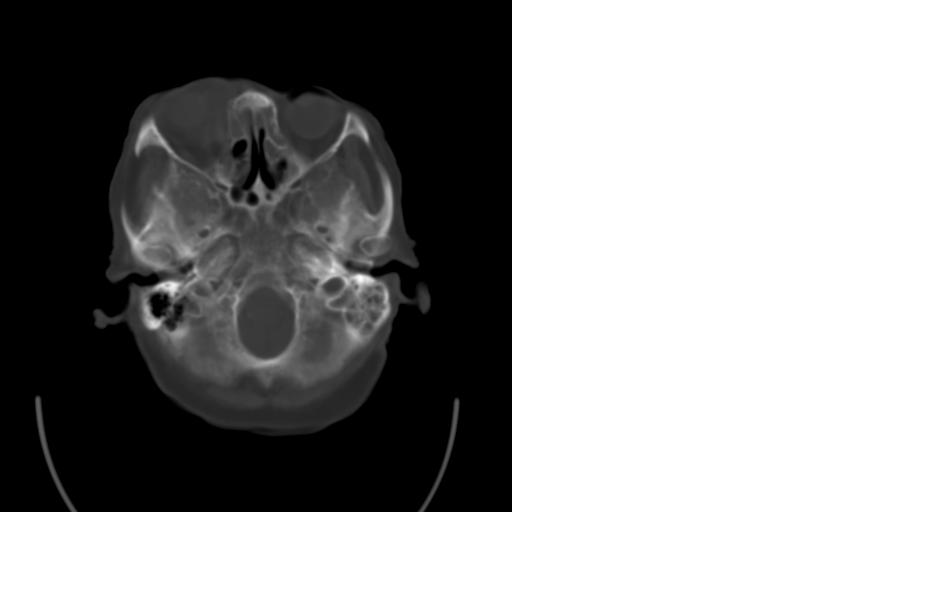

女,77岁,渐进性突眼2年,无其他明显症状

病变位于起源于右侧筛窦,右侧眼球受压移位,右侧大脑半球额叶白质受压塌陷,水肿不明显.额骨呈压迫性骨质吸收变薄.考虑脑膜瘤,建议增强吧

右侧额部软组织密度肿块,界限不清,明显向前下方增长,占位效应明显,内见钙化,局部颅骨明显吸收.考虑:右额叶脑膜瘤.建议:增强

右额窦粘液囊肿,向前累及筛窦并进入眼眶使眼球前突;向下进入颅内右额叶脑质及侧脑室受压

病变应起源于右侧额窦/或额骨板障,肿块周围骨包壳尚完整,呈膨胀挤压改变,右侧眼球受压移位,右侧大脑半球额叶白质受压塌陷,水肿不明显.考虑为良性病变,骨纤维瘤/或骨嗜酸性肉芽肿? 建议增强吧

支持:病变的起源我乐意定在右额窦。右额窦粘液囊肿或粘液腺癌累及筛窦、眼眶使眼球前突;向下进入颅内右额叶脑质及侧脑室受压变形。

右侧筛窦类圆形实质性肿块向颅内呈膨胀性生长,边缘较为光滑,其内似见囊性低密度影,边缘骨壁受压变薄移位,部分骨质缺损破坏

定位:来源右额窦。定性:良性占位—额窦黏液囊肿。理由1、病灶中心位于右额窦区,侵及筛窦并向下向前压迫眼球2、骨质呈膨胀性改变,骨质弓形变薄但骨壳完整,如为恶性骨质应为侵蚀性破坏3、黏液囊肿好发于筛窦、额窦。